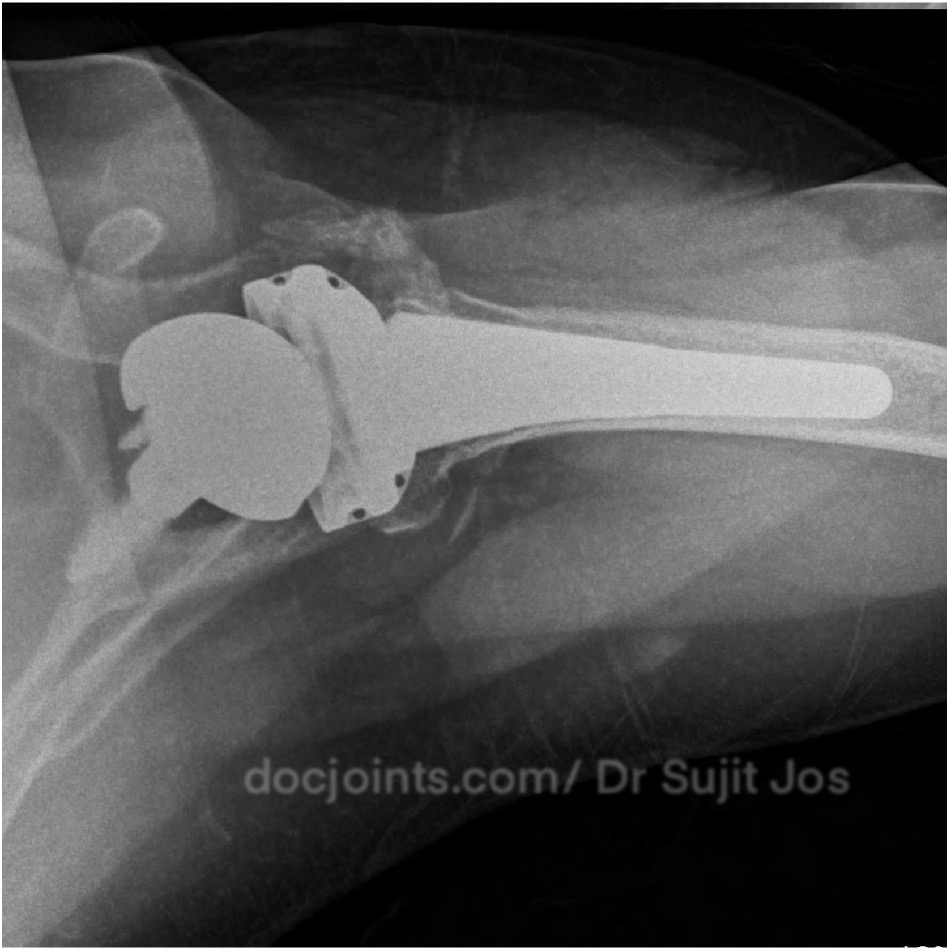

Re Retear of Rotator cuff repair done elsewhere. Failed Rotator Cuff Repair Managed with Reverse Shoulder Arthroplasty

At this stage, we discussed the available options with her. Considering her age, the condition of the joint, and her previous surgeries, we recommended a reverse shoulder replacement — a procedure designed to restore function even when the tendons are no longer working.

The surgery went smoothly.

Today, one year after surgery, she is one of our happiest patients.

She moves her shoulder comfortably. She sleeps peacefully. She lives independently again.